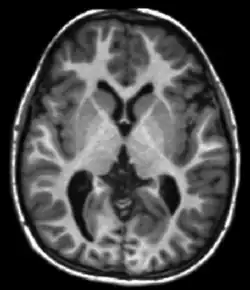

T1 is significantly different between grey matter and white matter and is used when undertaking brain scans. A strong T1 contrast is present between fluid and more solid anatomical structures, making T1 contrast suitable for morphological assessment of the normal or pathological anatomy, e.g., for musculoskeletal applications.

T1ρ MRI has been used to image tissues such as cartilage,[4][5] intervertebral discs,[6] brain,[7][8] and heart,[9] as well as certain types of cancers.[10][11]